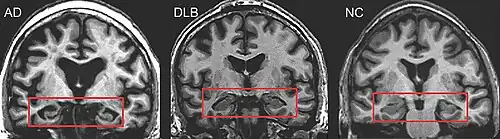

Direct laboratory-measurable biomarkers for DLB diagnosis are not known, but several indirect methods can lend further evidence for diagnosis.[24] The indicative diagnostic biomarkers are: reduced dopamine transporter uptake in the basal ganglia shown on PET or SPECT imaging; low uptake of 123iodine-metaiodobenzylguanidine (123I-MIBG) shown on myocardial scintigraphy; and loss of atonia during REM sleep evidenced on polysomnography. Supportive diagnostic biomarkers (from PET, SPECT, CT, or MRI brain imaging studies or EEG monitoring[121]) are: lack of damage to medial temporal lobe (damage is more likely in Alzheimer's disease[113]); reduced occipital activity; and prominent slow-wave activity on EEG.[24]

Lewy pathology affects the peripheral autonomic nervous system; autonomic dysfunction is observed less often in AD, frontotemporal, or vascular dementias, so its presence can help differentiate them.[136] MRI scans almost always show abnormalities in the brains of people with vascular dementia, which can begin suddenly.[137]

Dementia with Lewy bodies (DLB) is distinguishable from Alzheimer's disease (AD) even in the prodromal phase.[22] Short-term memory impairment is seen early in AD and is a prominent feature, while fluctuating attention is uncommon; impairment in DLB is more often seen first as fluctuating cognition.[138] In contrast to AD—in which the hippocampus is among the first brain structures affected, and episodic memory loss related to encoding of memories is typically the earliest symptom—memory impairment occurs later in DLB.[38][139] People with amnestic mild cognitive impairment (in which memory loss is the main symptom) may progress to AD, whereas those with non-amnestic mild cognitive impairment (which has more prominent impairments in language, visuospatial, and executive domains) are more likely to progress towards DLB.[140] Memory loss in DLB has a different progression from AD because frontal structures are involved earlier, with later involvement of temporoparietal brain structures.[139] Verbal memory is not as severely affected as in AD.[141]

PET or SPECT imaging can be used to detect reduced dopamine transporter uptake and distinguish AD from DLB.[56][144] Severe atrophy of the hippocampus is more typical of AD than DLB.[145] Before dementia develops (during the mild cognitive impairment phase), MRI scans show normal hippocampal volume. After dementia develops, MRI shows more atrophy among individuals with AD, and a slower reduction in volume over time among people with DLB than those with AD.[32] Compared to people with AD, FDG-PET brain scans in people with DLB often show a cingulate island sign.[32]